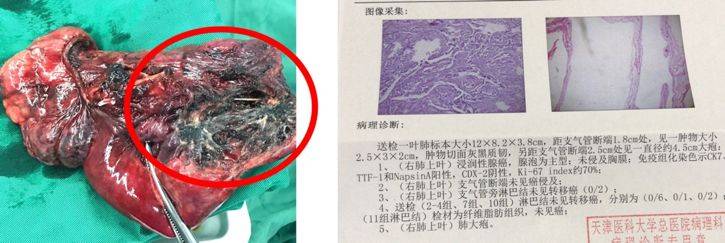

术后病理

组织学类型:(右肺上叶)浸润性腺癌,腺泡为主型;未侵及胸膜;支气管断端未见癌侵及;支气管旁淋巴结及2-4组、7组、10组淋巴结均未见转移癌。病理缓解率为60%。

图6. 术后手术标本及病理